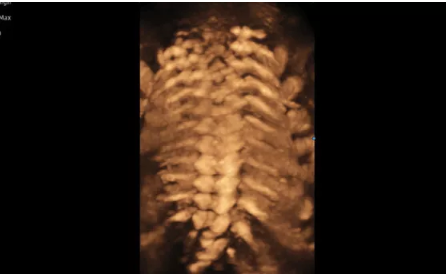

3D/4D成像方面,Hera i 10通過結合先進的圖像渲染技術,著重加強了邊緣和小結構的可視化能力。